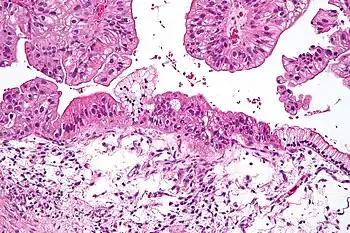

Mucinous adenocarcinoma

Mucinous adenocarcinomas make up 5–10% of epithelial ovarian cancers. Histologically, they are similar to intestinal or cervical adenocarcinomas and are often actually metastases of appendiceal or colon cancers. Advanced mucinous adenocarcinomas have a poor prognosis, generally worse than serous tumors, and are often resistant to platinum chemotherapy, though they are rare.[29]

Mucinous

Mucinous tumors include mucinous adenocarcinoma and mucinous cystadenocarcinoma.[29]